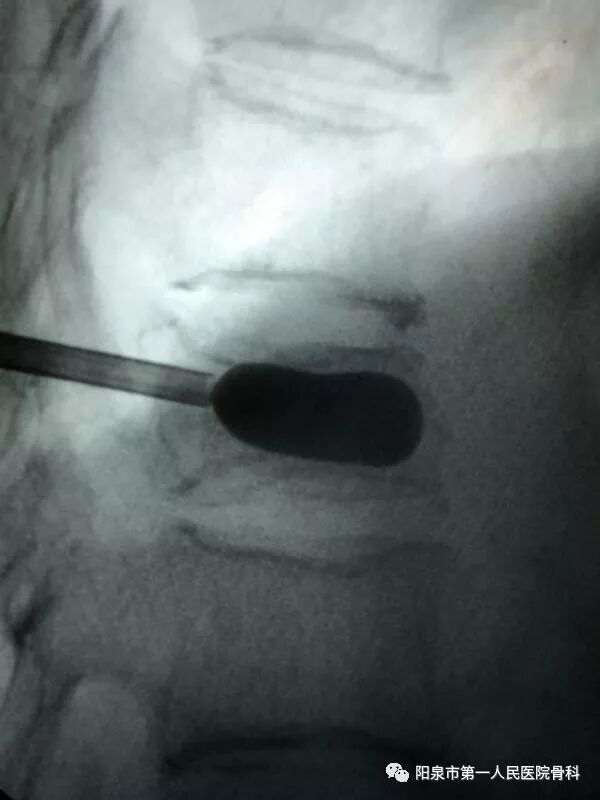

下面为在C臂机透视下观察到的穿刺操作过程,正侧位分别透视来确保正确的穿刺部位。图中黑色直杆为穿刺针。

椎体成型需要哪些器材椎体成形术概述_https://www.jmylbn.com_新闻资讯_第25张

后凸成形术时的球囊撑起显影图像